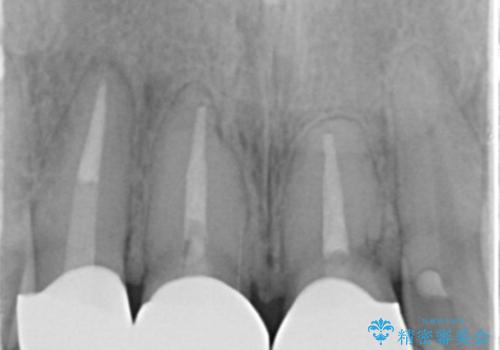

- 前歯(右上2)が黄色いとのことで来院。

レントゲンを撮ったところ前歯の被せ物が不適でした。

根管治療はご希望されなかったので(症状はなし)被せ物のやりかえ、右上2は被せ物の治療を行いました。